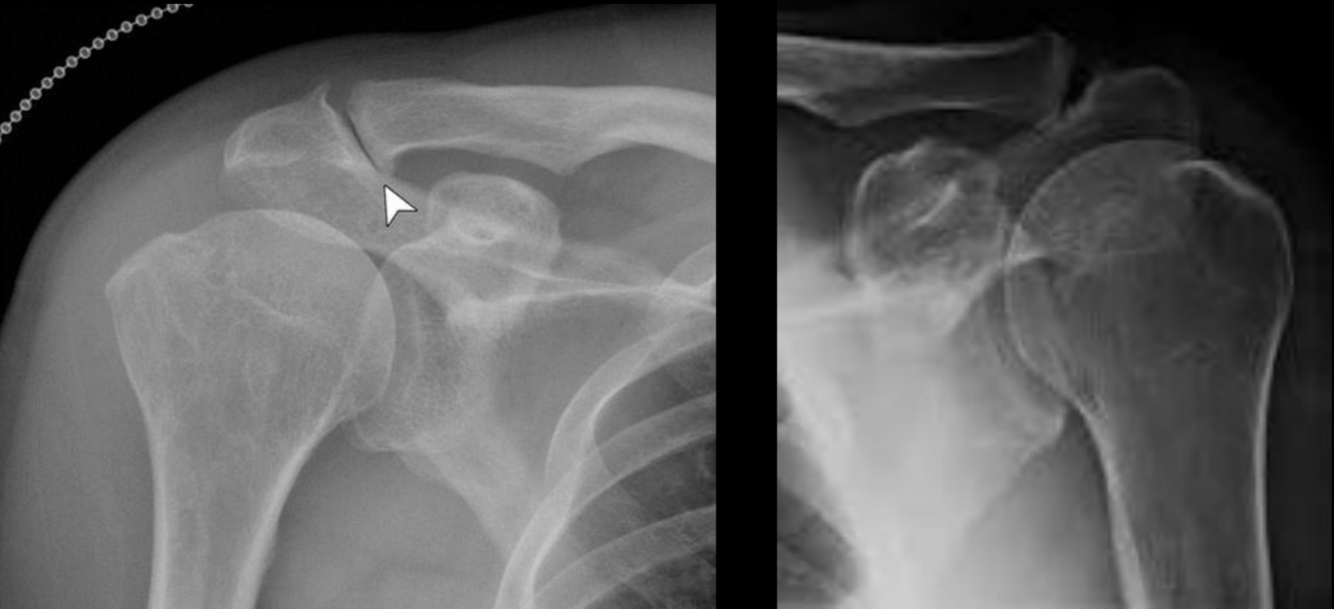

Datos rx que sugieren desgarro del manguito retador

Osteófitos acromioclaviculares

Disminución <7mm espacio subacromial

Irregularidad cabeza humeral